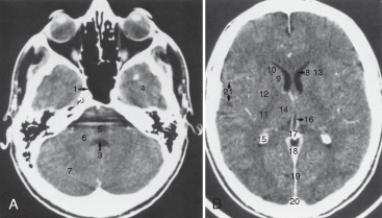

25

The falx cerebri is labeled:

A)17.

B)18.

C)19.

D)20.

27

The anterior (frontal) horn of the lateral ventricle is labeled as:

A)4.

B)8.

C)15.

D)16.

28

The thalamus is labeled:

A)9.

B)10.

C)12.

D) 14.

29

The internal jugular vein is labeled:

A)6.

B)7.

C)8.

D)9.

31

The structure labeled 15 is the:

A) calcified choroid plexus.

B) fourth ventricle.

C) pons.

D) third ventricle.

33

The structure labeled as 7 is the:

A) cerebellar hemisphere.

B) frontal lobe.

C) middle cerebellar peduncle.

D) temporal lobe.

37

The structure labeled 3 is the:

A) caudate nucleus.